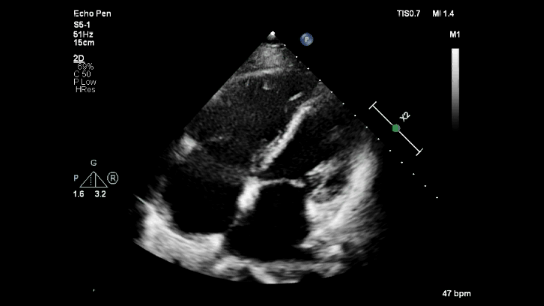

Echocardiography

Echocardiography in right ventricular myocardial infarction (RVMI) can resemble McConnell's sign.

Parasternal short axis reveals RV dilatation with preserved LV contraction.

RV dilatation with RV dysfunction with preserved apical contractility resembles McConnell's sign.

Three days following revascularization.